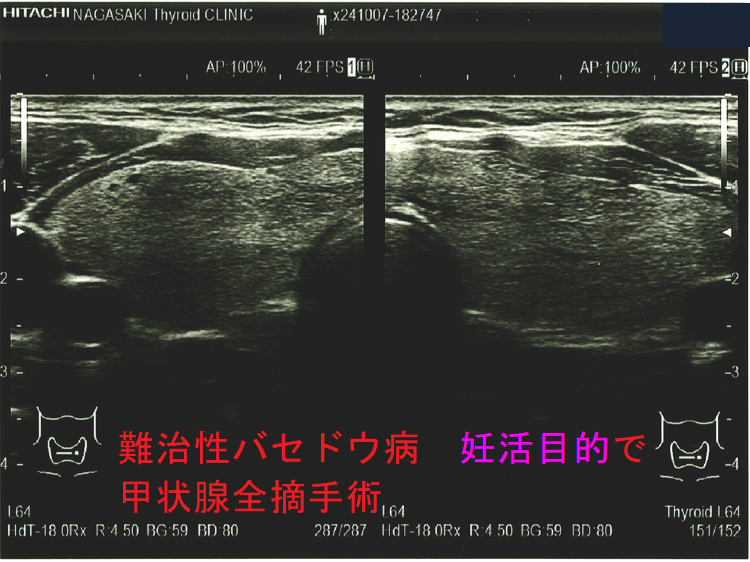

妊娠中、抗甲状腺薬(メルカゾール、プロパジール、チウラジール)+ヨウ化カリウム(KI)でもバセドウ病/甲状腺機能亢進症をコントロールできない時は、もはや妊娠2期(中期)の甲状腺全摘手術になります。[GUIDANCE TO THE MATERNAL, FETAL AND NEONATAL MANAGEMENT OF RESISTANCE GRAVE'S DISEASE IN PREGNANCY. Acta Endocrinol (Buchar). 2021 Oct-Dec;17(4):517-520.]

甲状腺全摘手術すれば母体の甲状腺機能は安定しますが、

- TSHレセプター抗体(TRAb)は急に下がらないため、妊娠20週以降に胎児の甲状腺を刺激して胎児バセドウ病、出生後の新生児バセドウ病は免れません。

- 妊娠3期(後期)の手術だと、母体の甲状腺ホルモンが胎児の脳下垂体にTSH(甲状腺刺激ホルモン)分泌抑制を掛けたままの出生になり、新生児一過性中枢性甲状腺機能低下症をおこす可能性があります。

妊娠中、抗甲状腺薬(メルカゾール、プロパジール、チウラジール)が副作用で使用できなくなった時は、妊娠2期(中期)に甲状腺全摘手術になります。妊娠1期(前期)に使用できなくなった時は、2期(中期)までヨウ化カリウム(KI)で持たせます。妊娠3期(後期)に使用できなくなった時は、出産後までヨウ化カリウム(KI)で持たせます。(第54回 日本甲状腺学会 P199 抗甲状腺薬の副作用のため手術療法を行い出産に至ったバセドウ病合併妊娠の一例)[Obstet Gynecol. 2013 Aug;122(2 Pt 2):490-492.][Korean J Intern Med. 2005 Dec;20(4):335-8.]